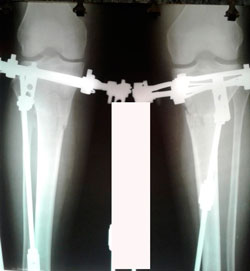

на фиксации

image-28-08-20-12-47-3.jpg

image-28-08-20-12-47-2.jpg

Дата операции - 05.08.2020

Дата снятия аппаратов - 10.12.2020